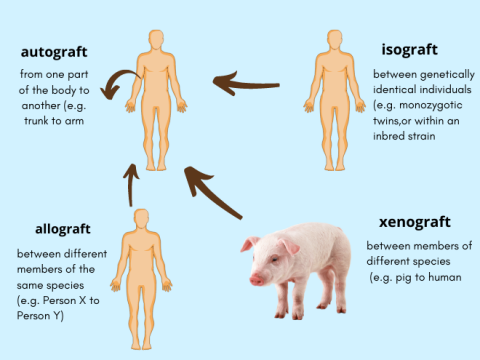

Types of Transplants or Grafts

Transplantation is the process of transferring cell, tissue or organ from one being to another. Now, they might be:

- Autograft: Tissue or organ is transplanted from one part of a person’s body to another part of the same person.

- Isograft: Tissue is transferred between genetically identical individuals (e.g., identical twins).

- Allograft: A tissue or organ is transferred from one person to another (same species, not genetically identical).

- Xenograft: Transplantation of organs or tissues between different species